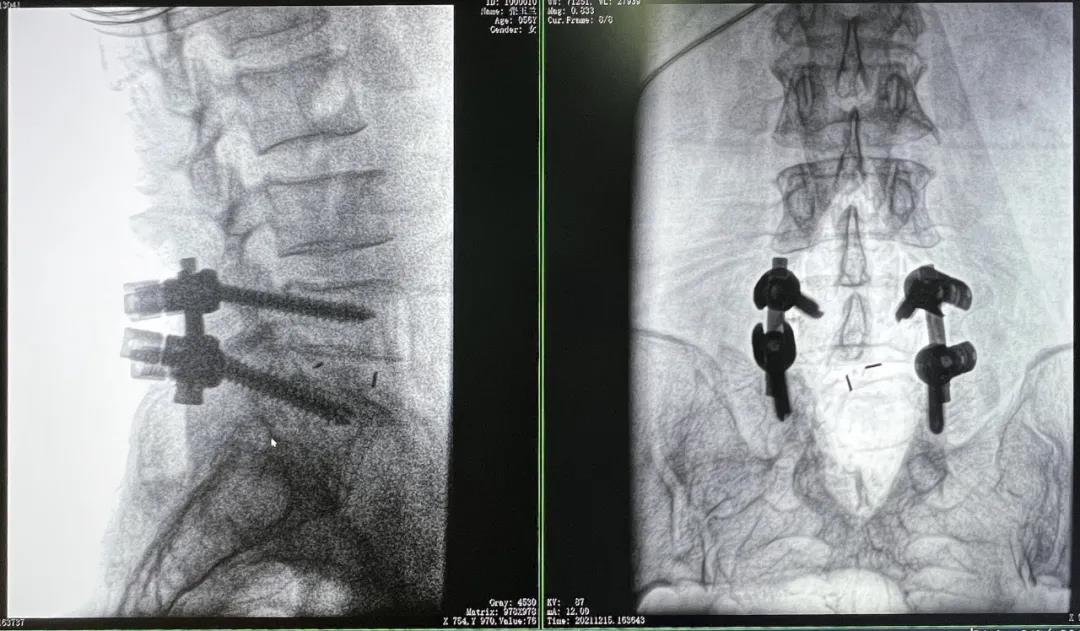

3D C形臂擺位及手術(shù)前二維影像

醫(yī)生在影像引導(dǎo)下在L5/S1椎弓根處打入醫(yī)用螺釘